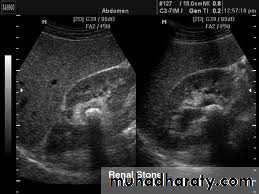

2-Stones larger than 5mm are easily seen on US but smaller ones may be missed.

-They produce intense echoes (hyperechoic) and cast acoustic shadows.

1-Dilatation of the P.C.S. appears as multilocular fluid collection within central echo complex.

-With more severe distention, dilated calyces appear as

Multiple cysts but communicating with each other unlike true cysts.